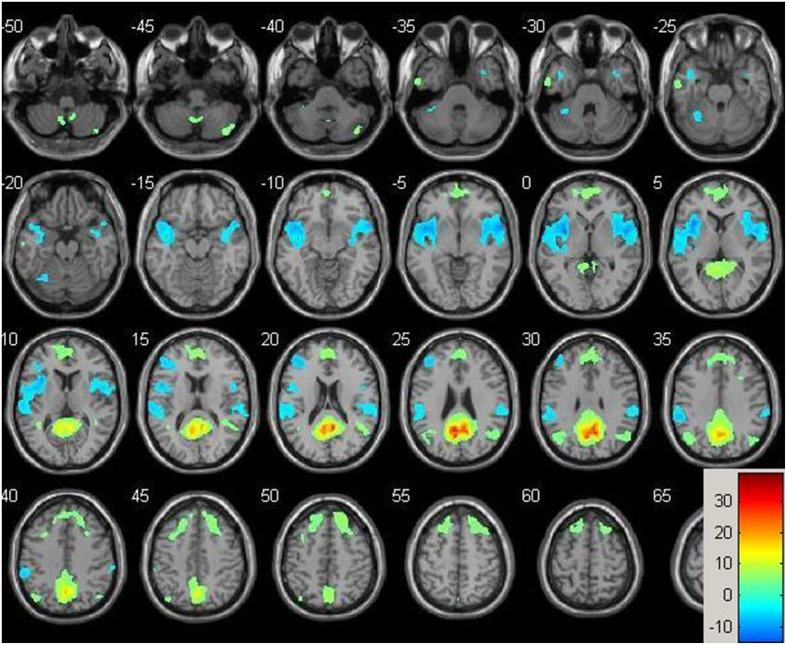

Computerized cognitive training (CCT) is a safe and inexpensive intervention to enhance cognitive performance in the elderly. However, the neural underpinning of CCT-induced effects and the timecourse by which such neural changes occur are unknown. Here, we report on results from a pilot study of healthy older adults who underwent three 1-h weekly sessions of either multidomain CCT program (n = 7) or an active control intervention (n = 5) over 12 weeks. Multimodal magnetic resonance imaging (MRI) scans and cognitive assessments were performed at baseline and after 9 and 36 h of training. Voxel-based structural analysis revealed a significant Group × Time interaction in the right post-central gyrus indicating increased gray matter density in the CCT group compared to active control at both follow-ups. Across the entire sample, there were significant positive correlations between changes in the post-central gyrus and change in global cognition after 36 h of training. A post-hoc vertex-based analysis found a significant between-group difference in rate of thickness change between baseline and post-training in the left fusiform gyrus, as well as a large cluster in the right parietal lobe covering the supramarginal and post-central gyri. Resting-state functional connectivity between the posterior cingulate and the superior frontal gyrus, and between the right hippocampus and the superior temporal gyrus significantly differed between the two groups after 9 h of training and correlated with cognitive change post-training. No significant interactions were found for any of the spectroscopy and diffusion tensor imaging data. Though preliminary, our results suggest that functional change may precede structural and cognitive change, and that about one-half of the structural change occurs within the first 9 h of training. Future studies are required to determine the role of these brain changes in the mechanisms underlying CCT-induced cognitive effects.

计算机认知训练(CCT)是一种安全且廉价的干预手段,可增强老年人的认知表现。然而,CCT 诱导效应的神经基础以及这些神经变化发生的时间进程尚不清楚。在这里,我们报告了一项针对健康老年人的试点研究结果,这些老年人接受了为期 12 周的每周 3 次、每次 1 小时的多维 CCT 方案(n = 7)或主动对照干预(n = 5)。在基线以及训练 9 和 36 小时后,进行了多模态磁共振成像(MRI)扫描和认知评估。基于体素的结构分析显示,右侧后中央回存在显著的组间×时间交互作用,表明与主动对照组相比,CCT 组在两次随访时的灰质密度均增加。在整个样本中,在后中央回的变化与 36 小时训练后的整体认知变化之间存在显著的正相关。事后顶点分析发现,在基线和训练后之间,左侧梭状回的厚度变化率在两组之间存在显著差异,以及右侧顶叶的一个大簇,覆盖了缘上回和后中央回。在训练 9 小时后,后扣带回与额上回之间以及右侧海马体与颞上回之间的静息态功能连接在两组之间存在显著差异,并且与训练后的认知变化相关。在任何光谱学和弥散张量成像数据中均未发现显著的交互作用。尽管初步研究结果,但我们的研究结果表明,功能变化可能先于结构和认知变化,并且大约一半的结构变化发生在训练的前 9 小时内。需要进一步的研究来确定这些大脑变化在 CCT 诱导的认知效应的机制中的作用。